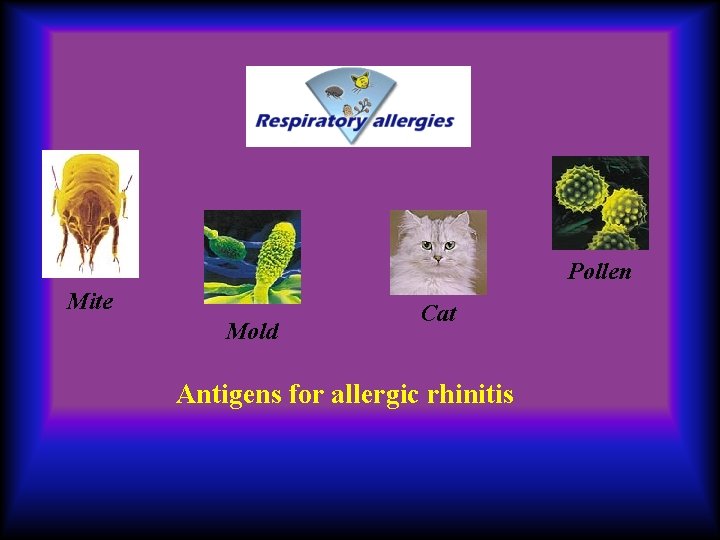

Pollen Mite Mold Cat Antigens for allergic rhinitis